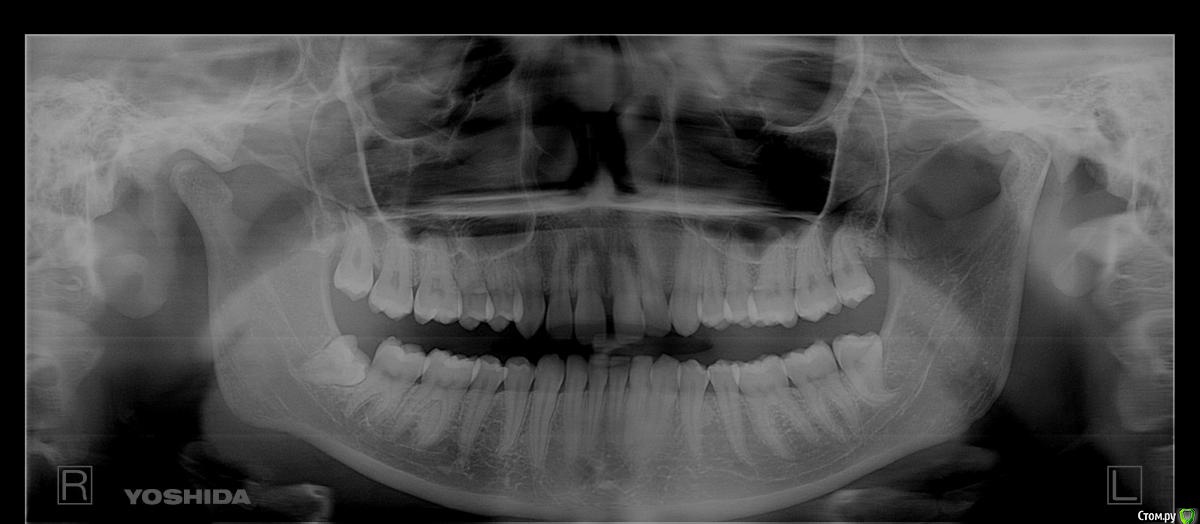

Павел7809 Опубликовано 19 декабря, 2016 Поделиться Опубликовано 19 декабря, 2016 (изменено) Уважаемые коллеги, собственно вопрос от моего пациента.Надо ли удалять все 8 зубы.Планируется ортодонтия. Я в этом соображаю мало поэтому прошу совета у вас... Изменено 19 декабря, 2016 пользователем Павел7809 Ссылка на комментарий

Павел7809 Опубликовано 19 декабря, 2016 Автор Поделиться Опубликовано 19 декабря, 2016 Так снимок же выложил Ссылка на комментарий

red_butler Опубликовано 19 декабря, 2016 Поделиться Опубликовано 19 декабря, 2016 Так снимок же выложилВидимо Вы его не сразу прикрепили. Все восьмые удалять. Ссылка на комментарий

Brigita Опубликовано 19 декабря, 2016 Поделиться Опубликовано 19 декабря, 2016 все восьмерки нужно удалить Ссылка на комментарий

Dok22 Опубликовано 11 января, 2017 Поделиться Опубликовано 11 января, 2017 Однозначно убирать. Ссылка на комментарий